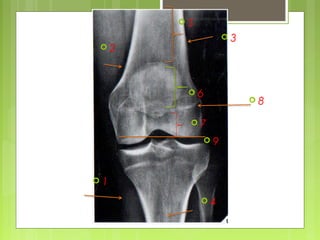

ESTUDIO DE UNA RX.

 Partes blandas, periostio, cortical,

medular ósea,

 Áreas comprometidas (diáfisis, metáfisis o

epífisis),

 Estado del cartílago de crecimiento y,

finalmente, afectación articular.

 2

 1

 3

 4

 6

 5

 7

 8

 9

Fémur normal